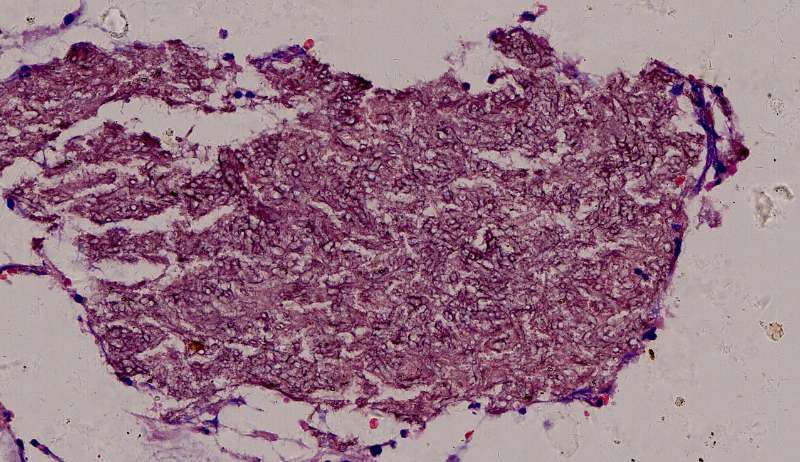

这些就是隐球菌,常被巨噬细胞吞噬,大多为多核巨噬细胞 隐球菌感染,在免疫力正常情况下,就是个肉芽肿 小白球,略显淡蓝色,这是荚膜的感觉

隐球菌在HE染色是小白球,隐隐的,球状的。在PAS染色是红色的小球,在六铵银染色是黑褐色的小球。

第二例隐球菌

整体是个类圆形,边界模糊(有晕征的感觉),肉芽肿一般都这样 里面也能见到许多小白球,大小从3微米到20微米不等 红细胞直径5-6微米 普通小淋巴细胞直径5微米 这里淋巴细胞挺多 有许多淋巴细胞,成堆

多核巨噬细胞吞了许多隐球菌 经常是反包围的感觉